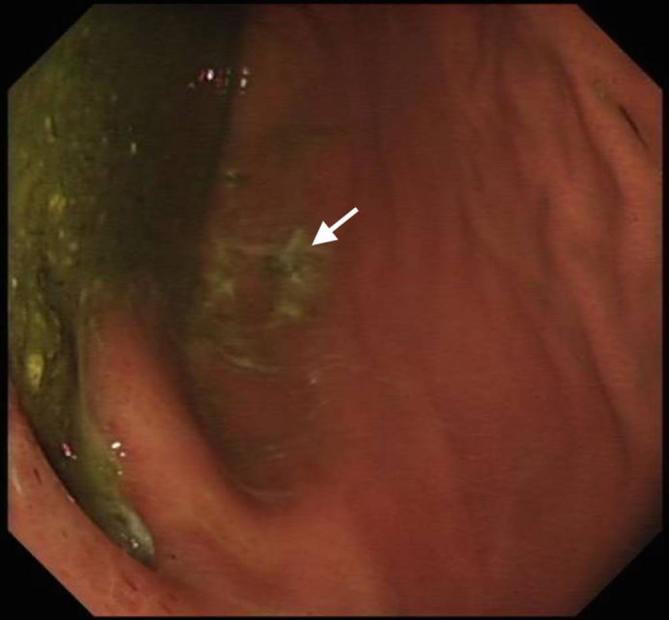

We report the case of an 84-year-old male, who presented with septicaemia, abdominal and back pain. The patient had a background of oesophageal carcinoma and had undergone previous oesophagectomy and gastric pull-up operation 10 years ago. A computerised topography scan demonstrated a probable gastro-vertebral communication with a destructive process at the T8/T9 vertebral level. Further evaluation with MRI clearly showed the tract between the two structures and confirmed the diagnosis of spondylodiscitis at the adjacent spinal level. The patient was resuscitated, treated with intravenous antibiotics and kept nil by mouth. A subsequent gastroscopy demonstrated an eroding gastric ulcer at the enteric opening of the tract between the tubal stomach and the spinal column. The diagnosis was discussed with the patient, his family and the surgical multidisciplinary team. Given the extent of disease and his multiple medical co-morbidities, the decision was made for conservative management and symptom control. This is the first case of a gastro-vertebral communication causing spondylodiscitis to be described in the literature.